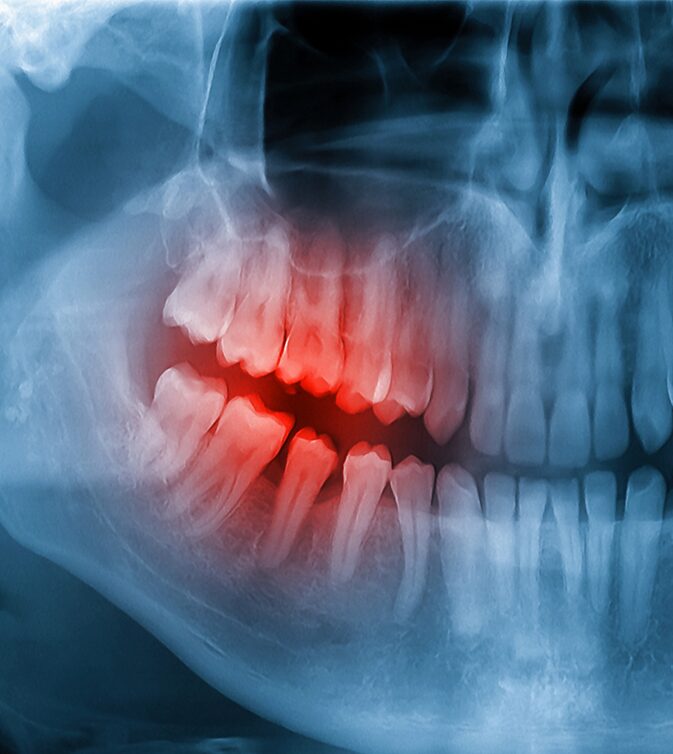

- Comprehensive examination and digital X-rays

- Infection and abscess management

- Root canal therapy when needed